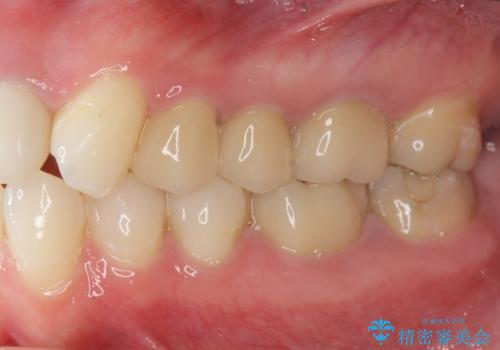

水銀を含む環境汚染金属アマルガムの除去 奥歯のセラミックインレー修復

- 古くなった銀歯を白くしたいとの希望で来院されました。

30年ほど前につめた水銀を使用する金属、アマルガム充填がなされていました。

アマルガムが飛散しないよう注意深く除去し、セラミックインレー修復を行います。

今回銀歯を白くされたいという希望でしたので、除去の際水銀を含むアマルガムが飛散しなよう細心の注意を払い、丁寧に除去したのちセラミックインレー(emaxプレスインレー)で審美的に修復を行いました。